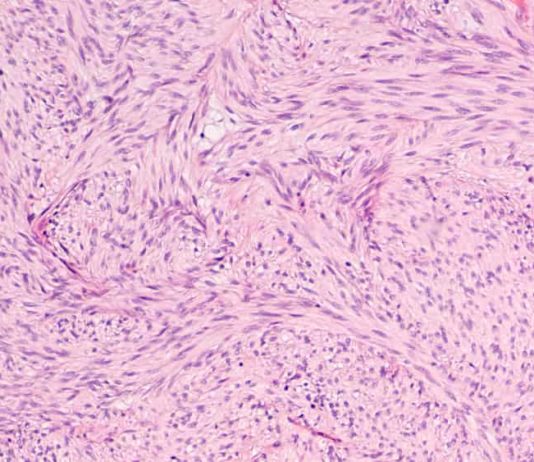

Apparato Digerente – Intestino, Fegato e Pancreas

INTESTINO

struttura e funzioni

Dopo aver subito i primi processi digestivi in sede gastrica, il bolo alimentare passa a livello intestinale dove la digestione viene completata e ha luogo il successivo assorbimento dei principi nutritivi contenuti nell’alimento.